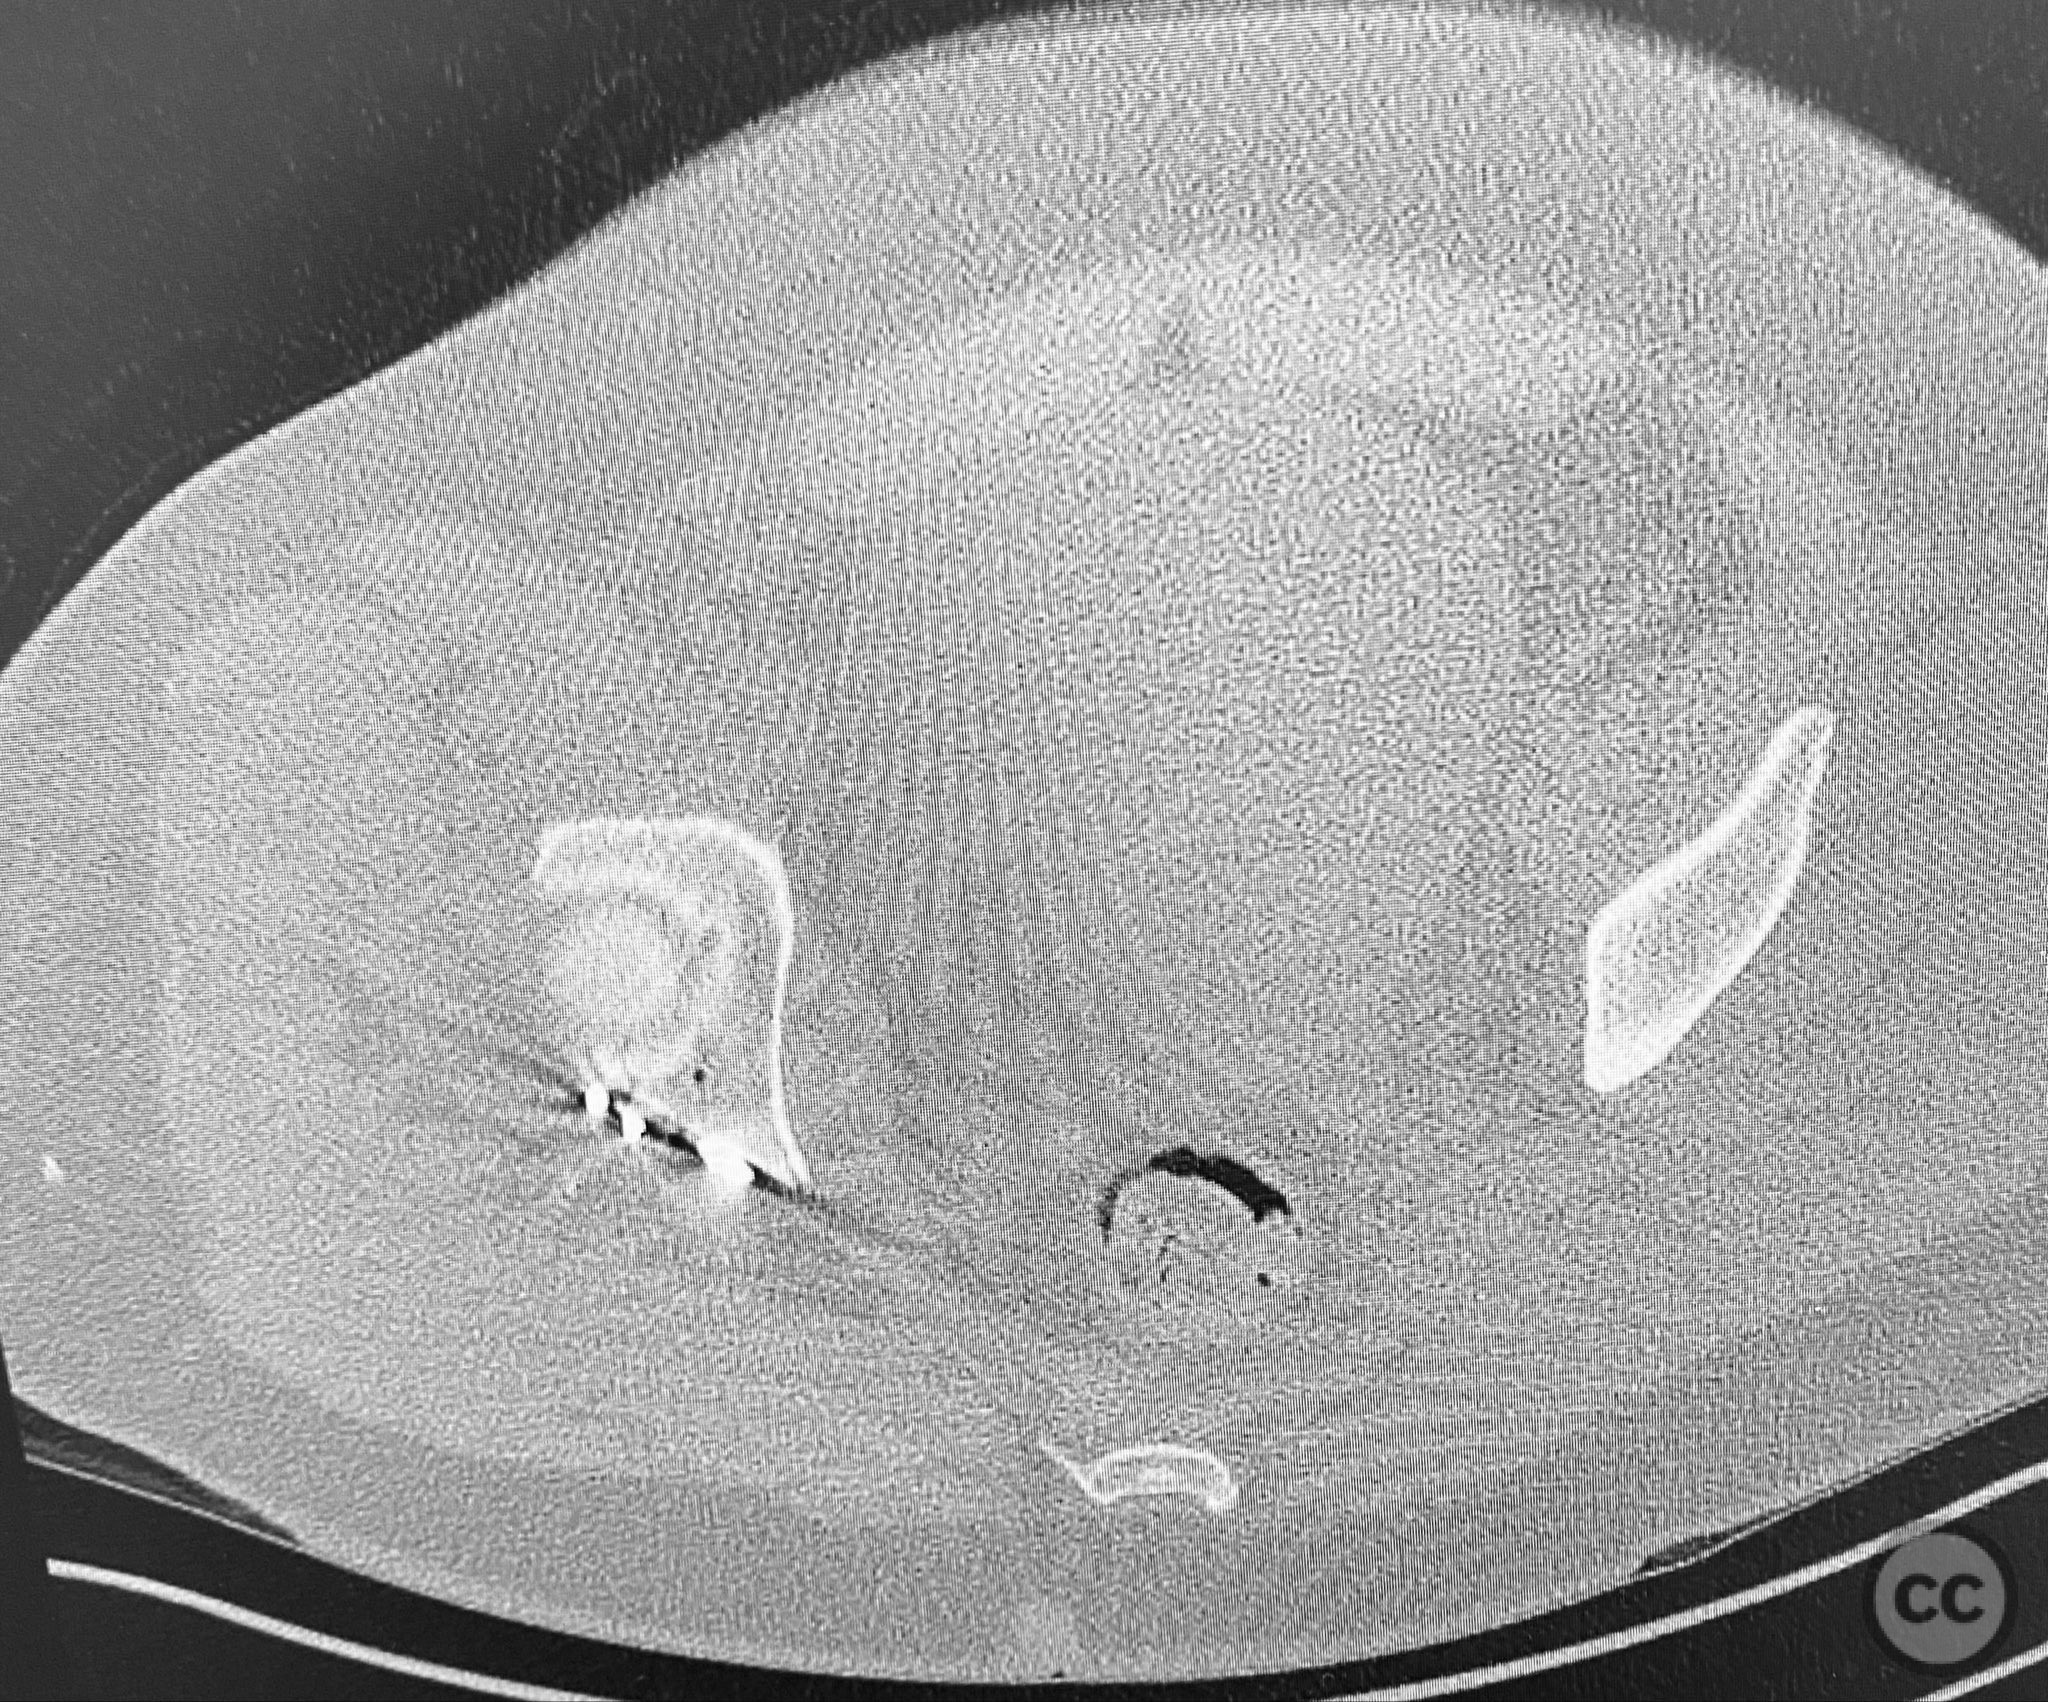

Clinical Details

Clinical and radiological findings:  A patient sustained a comminuted posterior wall acetabular fracture-dislocation (AO/OTA 62-B1.3) involving the greater sciatic notch, with associated traumatic sciatic nerve injury. Following closed reduction, imaging demonstrated an intra-articular fragment located within the acetabular fossa (fossa acetabuli). Clinical examination revealed neurological deficit consistent with sciatic nerve involvement. Radiographs and CT confirmed the extent of comminution and intra-articular displacement.